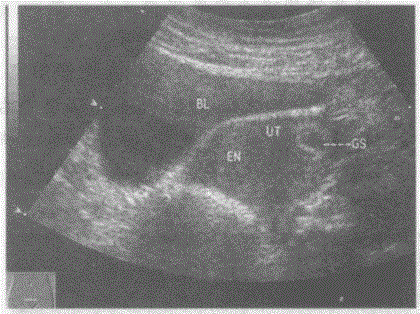

问题 临床资料:女性,27岁,自述停经50天。 化验检查:尿妊娠试验阳性。 超声综合描述:子宫形态失常,左右宫角不对称,左宫角膨出变钝,内见环状无回声,无回声内见胎芽及胎心搏动。 超声提示:

选项 A.左输卵管间质部异位妊娠 B.左卵巢异位妊娠 C.子宫角妊娠 D.腹腔异位妊娠

答案 C